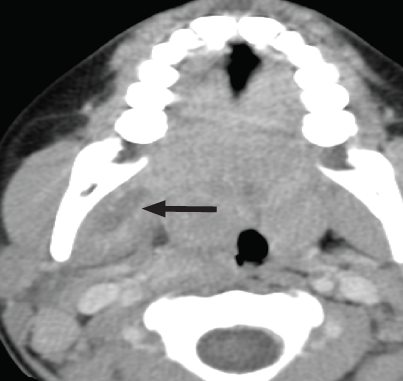

Masticator space abscess is the advanced form of a common odontogenic infection characterized by buccal pain, edema, and trismus. The common clinical signs of an adult masticator space abscess are jaw swelling and trismus following dental procedures. Masticator space abscess without dental operation is a rare infection that is typically detected in the infant with poor sucking, fever, irritability, and dehydration.

Mixed aerobic and anaerobic organisms, most often a-hemolytic streptococci, Bacteroides species, and Peptostreptococcus species are the most prevalent types of organisms that cause masticator space abscesses. Infants displaying such clinical signs require a comprehensive medical history and assessment. Ultrasonography (US) and computed tomography (CT) help confirm the diagnosis that is already evident from the patient’s symptoms.